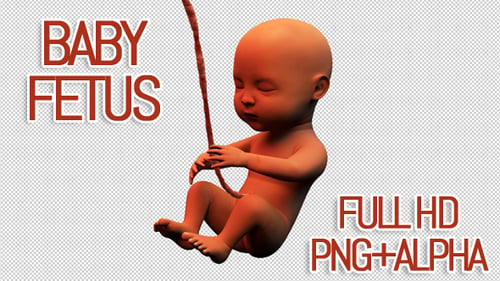

Animation médicale 3D d'un foetus humain

- Taille du fichier

- 203 MB

- Encodage vidéo

- Photo JPEG

- Orientation

- Horizontal